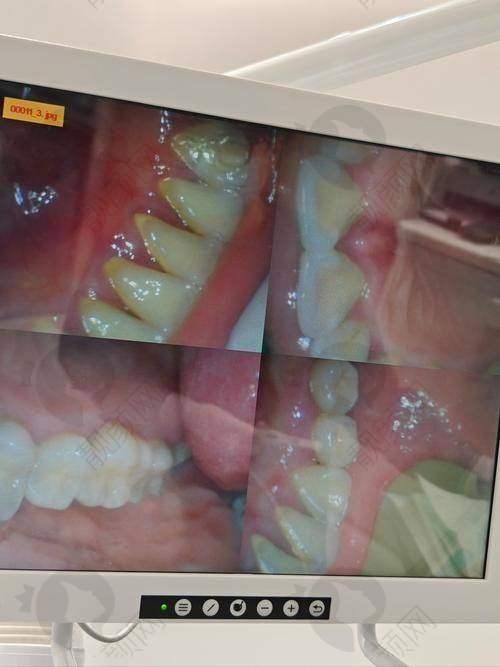

这50元起的洗牙价格,包含了专精的口腔检查、超声波洗牙以及牙齿抛光等一系列流程。医生会在洗牙前对您的口腔进行全方面检查,了解您的口腔状况,然后根据实际情况进行洗牙操作。洗牙过程中使用的是精良的超声波设备,能够有效去除牙齿表面的牙结石、牙菌斑和色素沉着。洗完牙后,还会对牙齿进行抛光处理,让牙齿更加光滑,减少牙菌斑的附着。